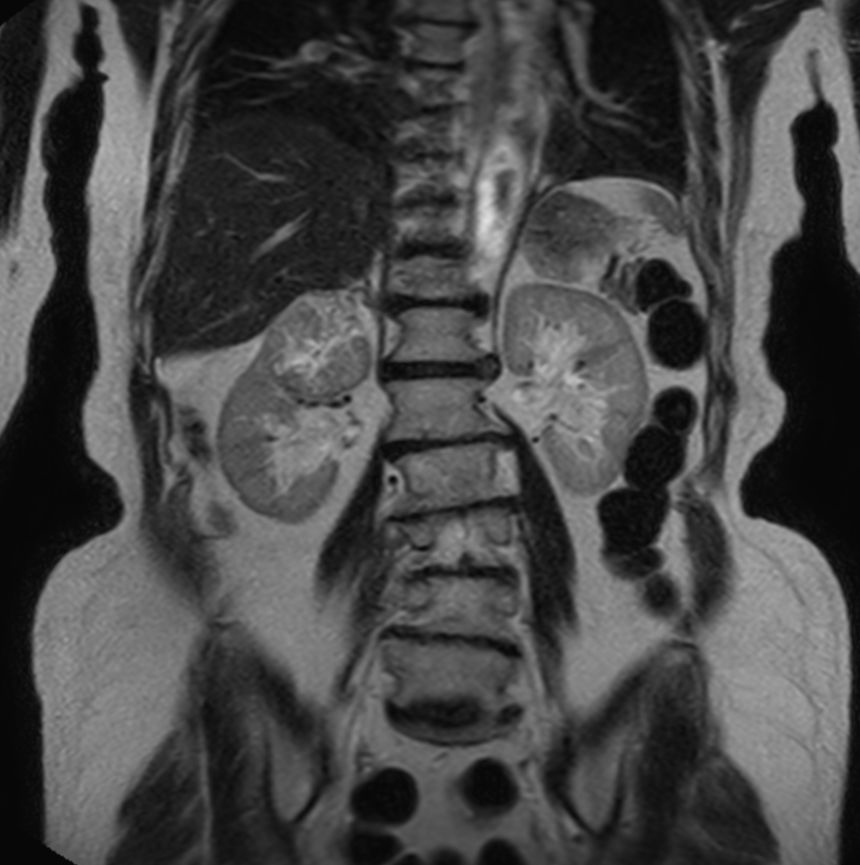

T2w TSE - Free Breathing

-